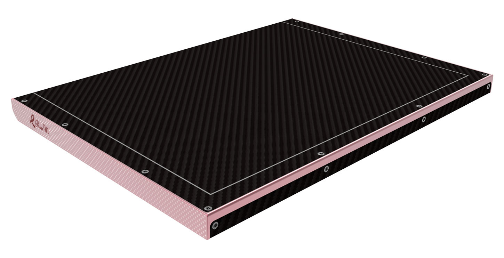

Шаг 4. Разновидности плоскопанельных матричных детекторов

Плоскопанельный матричный детектор представляет собой электронное устройство прямоугольной формы, размещенное в металлическом или пластиковом корпусе, который защищен карбоновым экраном. Карбон пропускает рентгеновское излучение, не оказывая влияния на качество изображения. Внутри корпуса находится светочувствительная матрица, которая может быть покрыта слоем сцинтиллятора, материал которого преобразует рентгеновское излучение в видимый свет. Сцинтилля́торы — это вещества, излучающие свет при поглощении ионизирующего излучения (гамма-квантов, электронов, альфа-частиц, электромагнитных волн рентгеновского излучения).

Существует два вида преобразования рентгеновского излучения в электрический сигнал:

1. Непрямое – рентгеновское излучение сначала преобразуется в свет при помощи сцинтиллятора, а затем в электрический сигнал при помощи светочувствительной матрицы из аморфного кремния (a-Si).

2. Прямое – рентгеновское излучение сразу преобразуется в электрический сигнал.

Такие плоскопанельные детекторы оснащены фотопроводником из аморфного селена (a-Se), который самостоятельно захватывает рентгеновские фотоны и преобразует их в электрический заряд.

Плоскопанельные детекторы прямого преобразования стоят существенно дороже детекторов непрямого преобразования, они чувствительны к окружающей среде, не переносят резких перепадов температур. Маммографы с такими приемниками предъявляют особые требования к стабильности питающей сети, а завод изготовитель зачастую рекомендует подключать оборудование к электросети лечебного учреждения через стабилизатор напряжения или через источник бесперебойного питания. При этом качество цифровых снимков, полученных с плоскопанельных детекторов прямого преобразования, существенно выше за счет большего соотношения сигнал/шума, больших значений функции передачи модуляции (MTF - Modulation Transfer Function) и квантовой эффективности регистрации (DQE - Detective Quantum Efficiency).